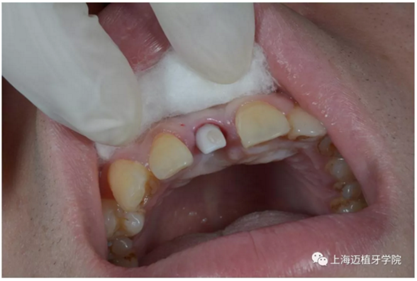

3月后恢復良好,上愈合基臺

2周后袖口成形

轉(zhuǎn)移模型

取工作模型